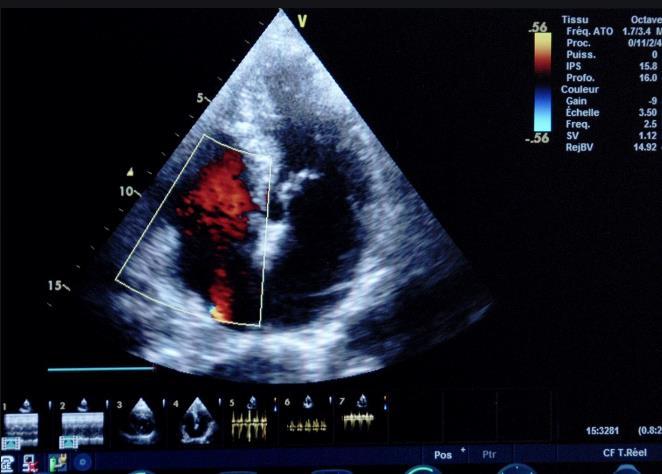

1左室右房分流的超声心动图特征